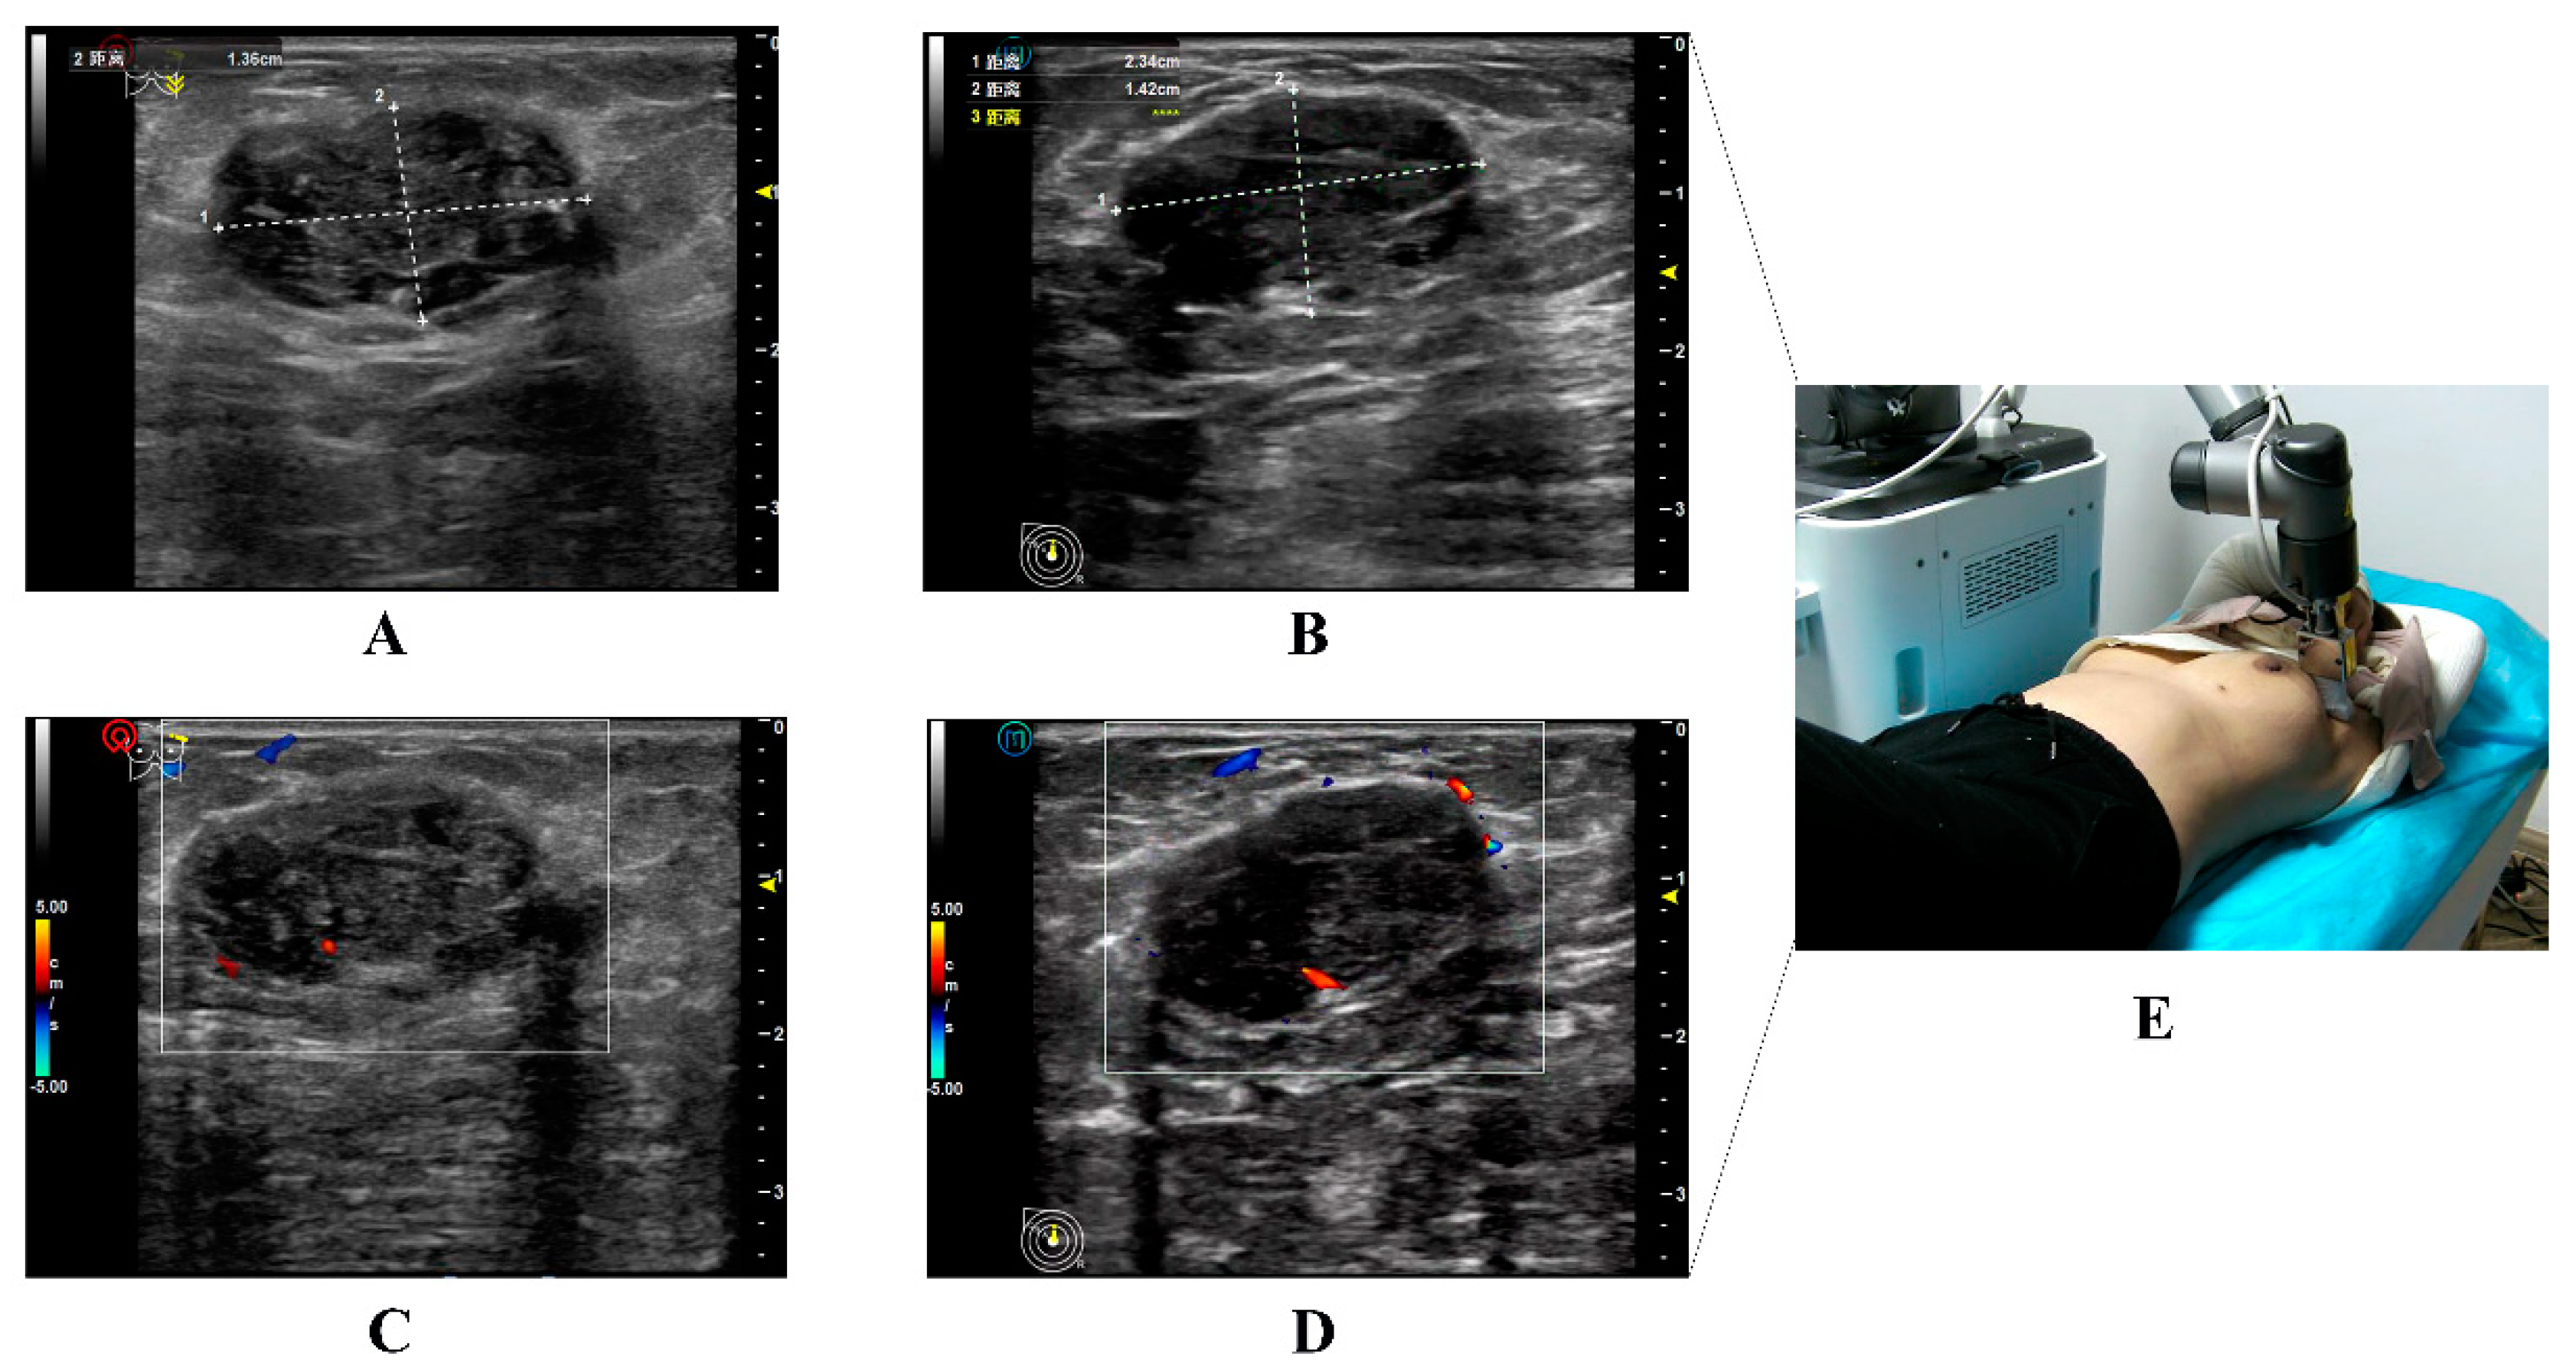

In Scenario A, 34 breast nodules were detected using 5G-based telerobotic US and 35 using conventional US. Moreover, 32 breast nodules identified on 5G-based telerobotic US examination were consistent with those detected on conventional US examination (Figure 4). In addition to the breast nodules, two cases of gynecomastia, one of lactation mastitis, and one of postoperative breast effusion were diagnosed using both these US procedures.

Figure 4.

Illustration of the ultrasound images of the same target nodule in a 36-year-old woman obtained from conventional and 5G-based telerobotic ultrasound examinations. Grayscale US images of the same breast nodule from the (A) conventional US examination and (B) 5G-based telerobotic US examination. The US characteristics of the breast nodule are as follows: oval shape, parallel orientation, circumscribed margins, hypoechoic echo pattern, and posterior shadowing with no calcifications. The nodule is classified as BI-RADS 4. Colour Doppler flow images are from the (C) conventional US examination and (D) 5G-based telerobotic US examination. There are blood flow signals detected inside this breast nodule. (E) The transducer is located in the outer upper quadrant of the left breast. (US, ultrasound; 5G, fifth generation; BI-RADS, Breast Imaging Reporting and Data System).

The 5G-based telerobotic US examinations missed three breast nodules classified as BI-RADS 3. Among them, one breast nodule was located in the outer quadrant of the left breast in a 72-year-old woman, and two breast nodules were located in the outer quadrant of the right breast in two obese women with body mass indexes of 33 and 34. Conventional US examinations missed two breast nodules classified as BI-RADS 3 (Table 2).

A paired-sample t-test revealed no significant differences between the 5G-based telerobotic and conventional US examinations in the transverse and anteroposterior diameter measurements of the same breast nodules and axillary lymph nodes (Table 4). Good inter-observer agreement was observed in the US features of the same breast nodules for the parameters of shape, orientation, margin, echo pattern, posterior features, calcifications, and BI-RADS category between the 5G-based telerobotic and conventional US examinations (ICC = 0.893, 0.795, 0.874, 1.000, 0.963, 0.882, and 0.984, respectively) (Table 5).